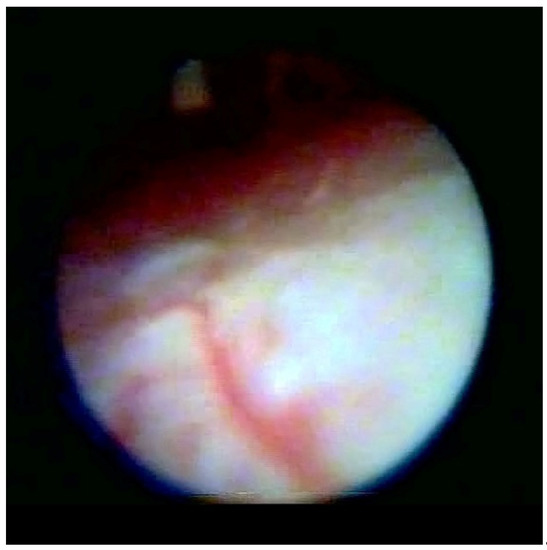

Figure 1 enables visualization of the composition of the normal dura and the other structure and directly indicates the absence of any median strand.

Figure 1. Normal dura in epiduroscopy.